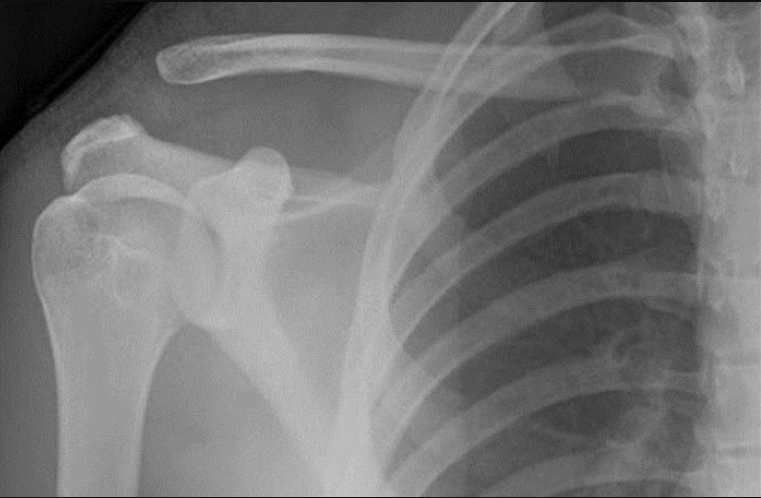

Hình ảnh trật khớp cùng đòn chụp x quang ở tư thế trước và sau

3. Hình ảnh trật khớp cùng đòn trên x quang ở tư thế trước và sau

- Chụp vai với các tư thế trước-sau, bên theo tiêu chuẩn, tuy nhiên chụp với tư thế Zanka cho cái nhìn rõ ràng nhất về khớp cùng đòn. Các tia X sẽ chiếu nghiêng khoảng 10-15 độ hướng lên đầu, để quan sát rõ nhất người bệnh nên xách mỗi bên khoảng 5kg và so sánh giữa 2 bên trên phim XQ.

Chụp với tia cường độ cao có thể cho phép phân biệt các dạng tổn thương giữa type I và II, đặc biệt quan trọng hơn trong phân biệt giữa type II và type III.